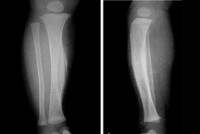

Синдром Мари-Бамбергера (системный оссифицирующий периостоз, гипертрофическая остеоартропатия) - избыточное разрастание костной ткани, описанное австрийским терапевтом Бамбергером и французским неврологом Мари. Проявляется множественными, как правило, симметричными гиперостозами, возникающими в области предплечий, голеней, плюсневых и пястных костей. Сопровождается характерной деформацией пальцев: фаланги утолщаются в виде «барабанных палочек», ногти приобретают вид «часовых стекол». Пациента с гиперостозом беспокоят боли в костях и суставах. Также наблюдаются вегетативные расстройства (покраснение и бледность кожи, потливость) и рецидивирующие артриты пястнофаланговых, локтевых, голеностопных, лучезапястных и коленных суставов со стертой клинической картиной. Возможно увеличение носа и утолщение кожи на лбу.Гиперостоз при синдроме Мари-Бембергера развивается вторично, как реакция костной ткани на нарушение кислотно-щелочного баланса и хронический недостаток кислорода. Причиной возникновения синдрома являются злокачественные опухоли легких и плевры, хронические воспалительные заболевания легких (пневмокониоз, туберкулез, хроническая пневмония, хронический обструктивный бронхит ), болезни кишечника и почек, а также врожденные пороки сердца. Реже наблюдается при циррозе печени, лимфогранулематозе и эхинококкозе. В ряде случаев гиперостоз возникает спонтанно, без связи с каким-то заболеванием.

На рентгенографии голеней, предплечий и других пораженных сегментов выявляется симметричное утолщение диафизов вследствие образования гладких, ровных периостальных наслоений. На начальных стадиях плотность наслоений меньше, чем у кортикального слоя. В последующем наслоения становятся более плотными и сливаются с кортикальным слоем. При успешном лечении основного заболевания проявления синдрома Мари-Бембергера уменьшаются и даже могут полностью исчезать. Для уменьшения болей в период обострения применяются НПВС.